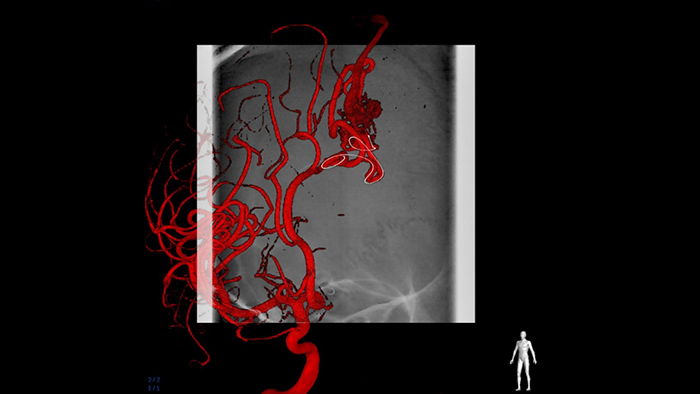

SmartCT Angio fournit une vue volumétrique en quelques secondes pour faciliter l’évaluation des artères nourricières, des veines drainantes, des veines artérialisées, du nidus et de la pathologie rompue ou non rompue afin de guider la prise de décision. Les volumes 3D sont visualisés avec une haute résolution spatiale et une compensation automatique des mouvements du patient pour améliorer la visibilité des détails critiques.

La possibilité de visualiser l’anatomie vasculaire submillimétrique améliore les chances de succès et augmente la fiabilité dans le traitement. SmartCT Vaso fournit une imagerie 3D haute résolution qui révèle des informations clés sur les structures vasculaires cérébrales afin de permettre une évaluation spatiale optimale des vaisseaux dans le contexte des tissus mous.

L’outil SmartCT Roadmap offre une superposition d’images 3D en temps réel pouvant être segmentée afin de mettre en évidence le vaisseau et les lésions cibles, permettant ainsi d’accélérer la navigation du cathéter. SmartCT Roadmap superpose une reconstruction 3D de l’arbre artériel, des segments de vaisseaux ou des annotations à des images fluoroscopiques en temps réel.